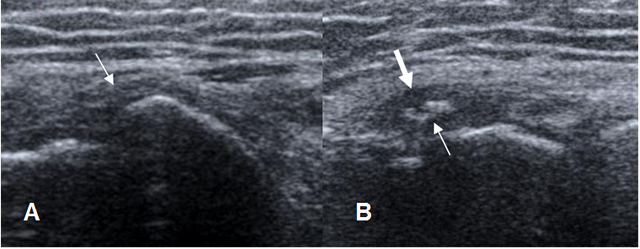

Fig 49 B. Ruptura parcial.

Ecografía en vista longitudinal. Solución de continuidad en fibras, sobre el origen conjunto de

los tendones extensores sobr el epicóndilo lateral, por ruptura parcial.

Fig 49 D. Epicondilitis lateral.

A: Ecografía sagital. Apariencia normal en el origen común de los tendones extensores.

B: Ecografía sagital. Origen de tendones engrosado e hipoecoico, por cambios inflamatorios. (Flecha gruesa). Muestra áreas ecogénicas por fibrosis secundaria a tendinitis crónica o ruptura parcial. (Flecha delgada).